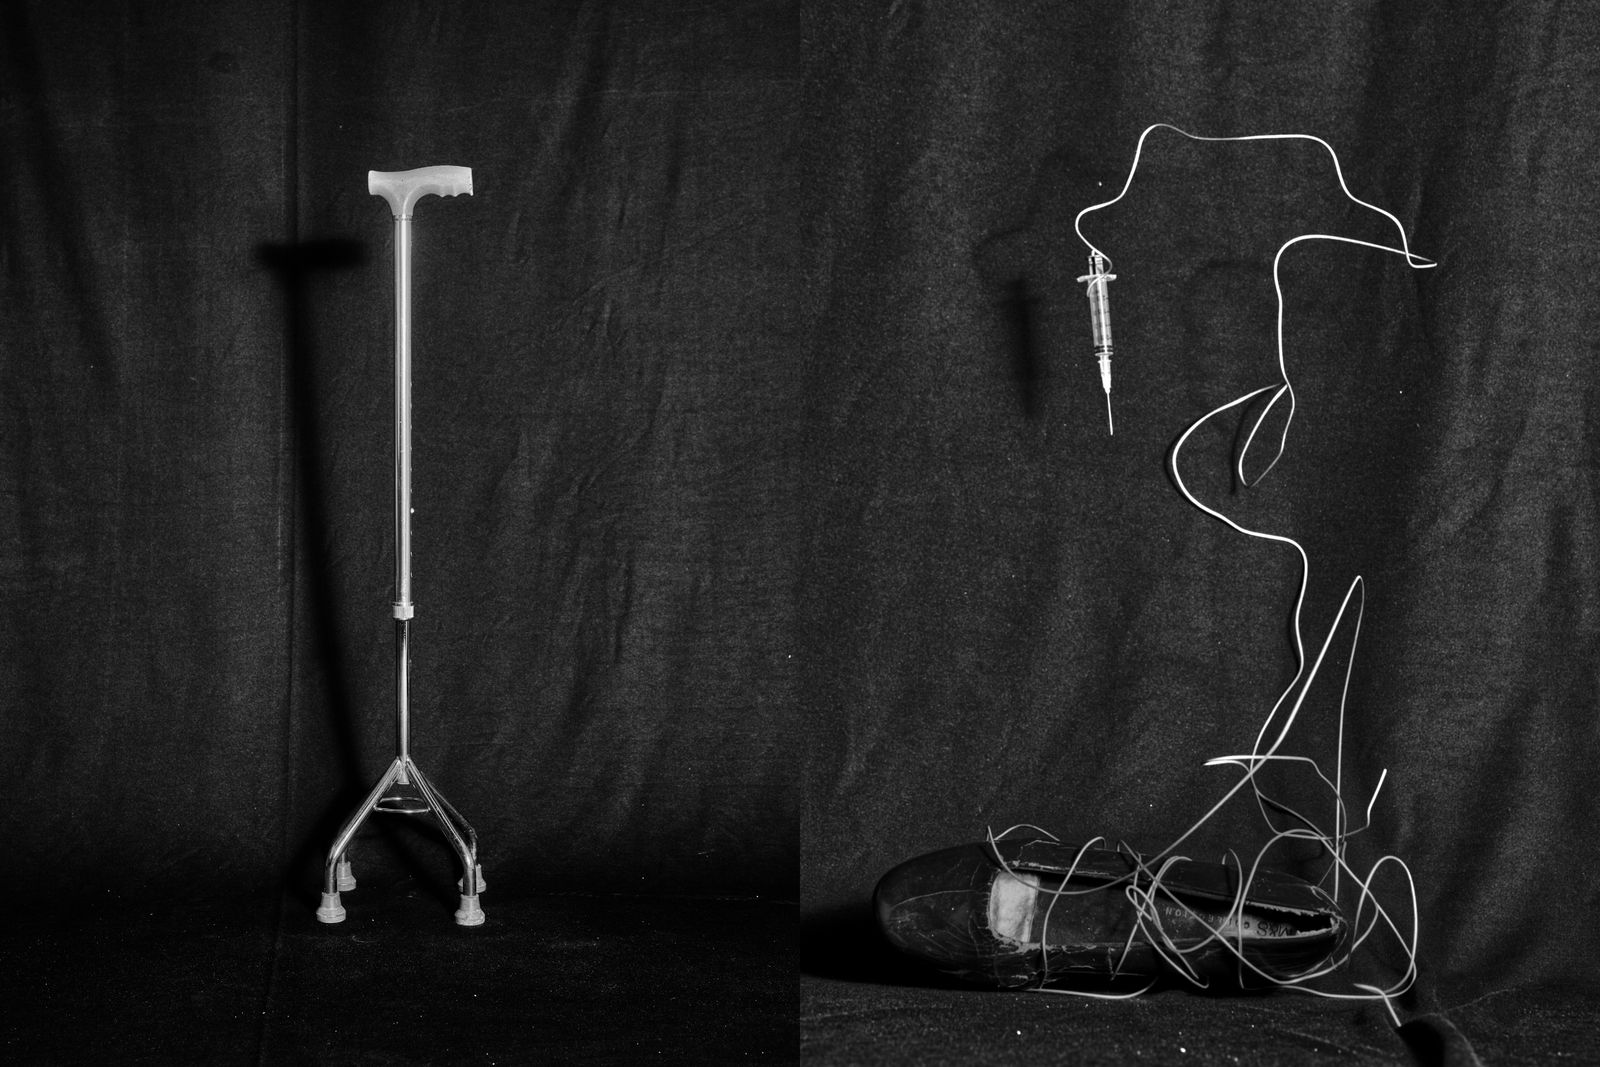

In There Is No Other Home I explore Still-Life, text, sculpture and mixed media experiments to address the Non-Linearity of Healing, and depict healing as a loop. Using staged photography I reflect on how trauma rewires both memory and body. The images move between absence and presence, rupture and repair, exploring the tension of detachment and reattachment to one’s own body.

There Is No Other Home emerges from the space between chaos and understanding. My body often feels like it carries its own memory. My hands loose grip, I stumble more often, and I freeze at things others take for granted, like driving. I return to fragments of memory, my mother’s CT scan when she was carrying me and my twin sister, a childhood photograph, not as evidence of illness but as traces of fragility, endurance, and survival.

Working with hands became central. Sensations of tingling in my fingers was the first sign of my illness, so I sculpted and cast hands as a way to confront the absence of movement.

In this process of self-discovery, camera became both my weapon and my shield. I reimagine Photography as a tactile language of healing, a space to witness, question, and accept the scattered parts of self. There Is No Other Home reveals the paradox of art as both a form of control and a confrontation with chaos, where making becomes a physical encounter with trauma and healing. The hands I sculpted became more than metaphors, they turned into a tangible form of trauma, making visible what is normally invisible to the eyes.